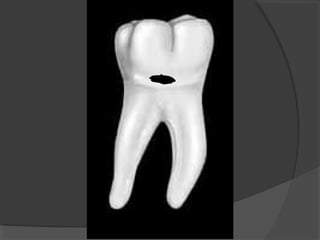

a) Class I Cavities:

Those cavities originating in anatomical pits and

fissures. They are found in the occlusal surface of

molars and premolars.